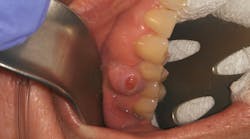

Patient: 40-year-old female

- Recurrent anterior mandibular swelling

- Two prior surgeries over the past six years to correct the condition

- Lesion previously removed when it was small and asymptomatic

- Patient pursued herbal treatment after second surgery